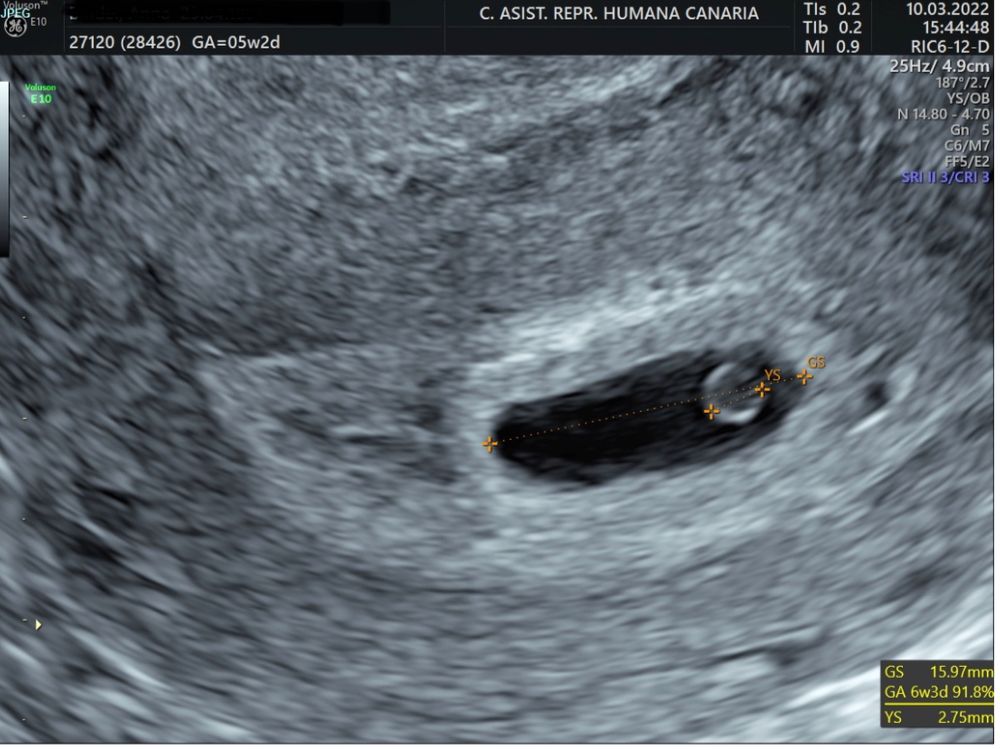

Первое узи в 5 недель и 2 дня

А круглый шарик -это желточный мешочек? тихонечно поздравляю Вас 🤰💐

Поздравляю вас💐❤️ Скажите, пожалуйста, какой это дпп был и какой размер ПЯ и ЖМ по УЗИ?